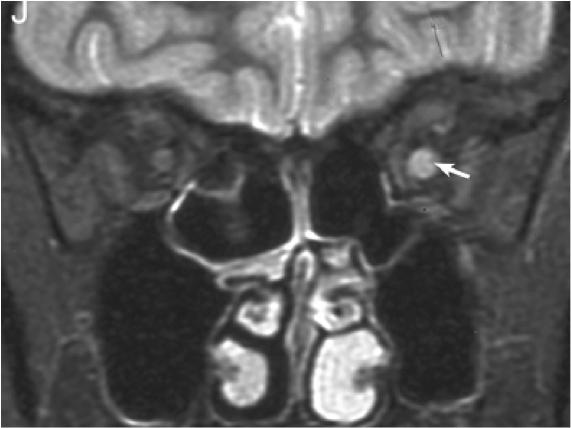

2. NMOSD 视神经MRI:病变较长,累及视交叉